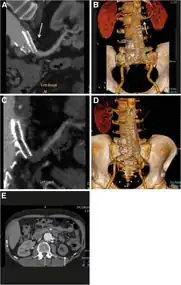

Diagram of renal artery stenosis